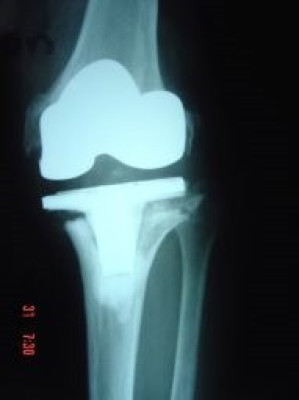

Revisión de prótesis de rodilla

Envíado por Dr. Ricardo Antonio Gómez G.